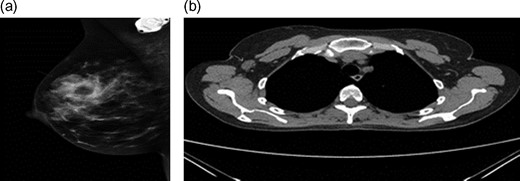

A 43-year-old female, 10 weeks postpartum, underwent colonoscopy for bleeding per rectum showing a bulky tumour (Fig. 1) in the rectum at 5 cm. Histologically poorly differentiated adenocarcinoma of the rectum (Fig. 2) T3N1Mo. Underwent laparoscopic loop ileostomy formation for impending bowel obstruction. Bloods showed Hemoglobin13.6 g/dL, Bilirubin 10umol/L, CEA 3.6 ng/mL. MRI pelvis (Fig. 3a and b) showed locally advanced annular neoplasm of mid and upper rectum. CT TAP (Fig. 4) reported no distant metastasis. She had neoadjuvant chemoradiothreapy with poor response. Post chemotherapy she noticed a lump in her right breast and axilla. Breast mammogram (Fig. 5a) showed 26 mm lesion in the right breast at 10 o'clock position and ultrasound showed 27 mm lesion in right axilla. Core biopsy (Fig. 6) reported signet ring morphology. The tumour stained positive with CK20, CDX-2 and CEA. There was no staining with CK7, ER, PR or Her-2. The rectal biopsy specimen, also analysed for KRAS status, was KRAS/NRAS/BRAF negative. She is being followed up by oncology with FOLFOX+Panitumumab.

(a) Mammogram post-neoadjuvant chemoradiothreapy showing right breast mass. (b) CT TAP pos-tneoadjuvant chemoradiothreapy showing enlarged right axillary lymph node.

Differentiating primary from metastatic breast neoplasms is not always easy. Mammograms help in settling doubts. The classic mammographic finding is a rounded, well-circumscribed mass no speculation, microcalcification or thickening of the skin [1, 4]. Typical ultrasound (US) features of haematogenous metastases include single or multiple, round to oval shaped, well-circumscribed hypo-echoic masses without spiculations, calcifications, or architectural distortion located superficially in subcutaneous tissue or immediately adjacent to the breast parenchyma.